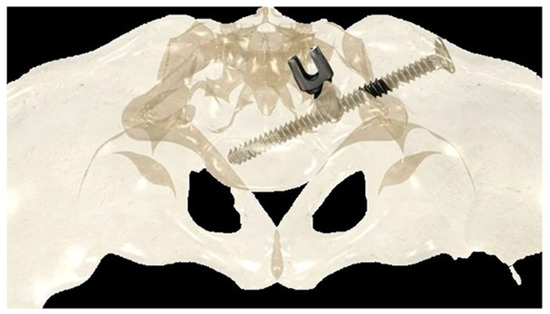

2.2.1. Iliosacral Screws

If the construct included the pelvis, an initial short midline incision was made at the lumbosacral junction. A Wiltse intramuscular paramedian approach was used to expose the lumbosacral joint and posterior cortex of the sacrum on each side. A small hole was then created in the sacral cortex, lateral to the articular process of S1, and above the first posterior sacral foramen. An iliosacral connector is inserted into the sacral hole. This connector has a deep ring, into which an iliosacral screw is introduced percutaneously using a bespoke jig, following an oblique posteroanterior direction that avoids the spinal canal, starting from the iliac crest and ending in the body of S1 (Figure 2). The open and polyaxial iliosacral connector allows an easy and secure connection of the rod to the iliosacral screw. The connector has a low profile and is located in a deep position, allowing its use in very young and skinny patients with a body weight of less than 15 kg.

The deep intraosseous direction of the iliosacral screw provides strong and stable pelvic fixation that can be used in all conditions, especially in neuromuscular patients with very osteoporotic bone [26,27].

Figure 2. Drawing showing the bony path of the iliosacral screws passing through the ring of the iliosacral connectors.